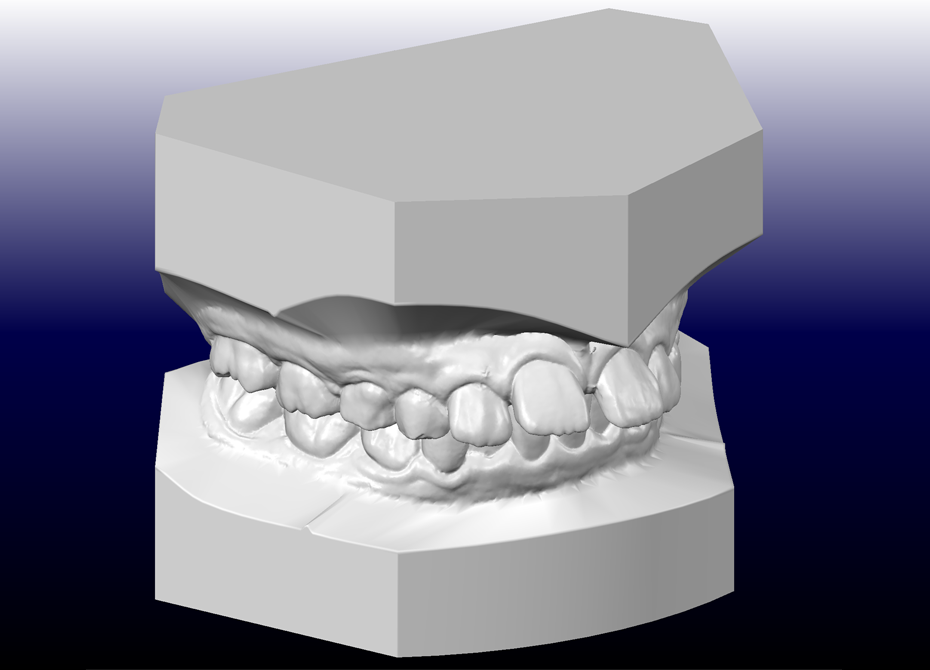

デジタル模型

採得したデジタルデータを、コンピュータ解析します(セファロ分析および治療シミュレーション)。 また上下顎骨の前後的および垂直的バランスを評価し、今後の成長を考慮した上で治療方針を決定します。 サリバテストでは、口腔内の細菌と唾液の性質を評価し、現在の口腔内環境に合わせた虫歯予防プランを作成します。 検査結果を元に十分な相談の上、できる限り希望に沿えるよう適切な治療の計画を立てます。